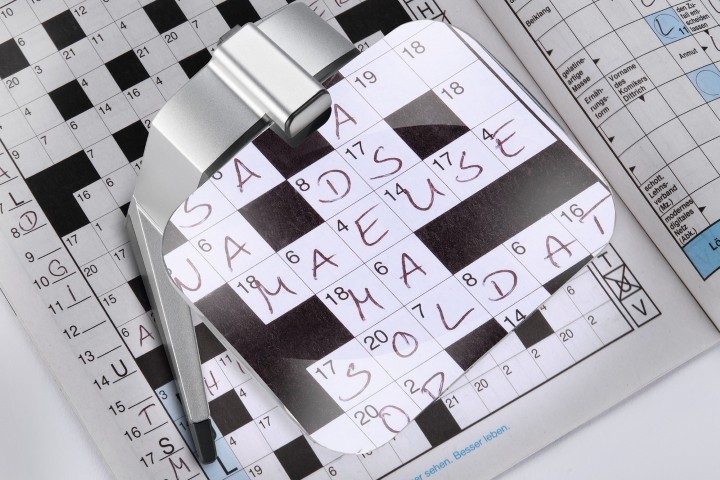

Fig 1A. An OCT thickness map is imported to the Navilas system and automatically registered and overlaid onto to a live fundus image. B. Treatment planning is done on a touch screen and laser treatment is delivered using real-time eye-tracking. Areas of the fundus, in this case the optic nerve, can be marked as no-go areas for the laser. A titration spot at the arcade is used to calculate an appropriate subthreshold power setting. C. At the end of laser treatment, an image is captured and a summary documenting areas of threshold (laser uptake visible) and subthreshold (no visible uptake) areas of treatment is produced

Given the chronicity and treatment resistance, a combined strategy using the Navilas navigated laser system was employed. This laser platform provides real-time eye tracking and precise treatment planning using a touchscreen interface3.

The precision offered by navigated laser systems proves particularly valuable for subthreshold treatments requiring confluent patterns. Real-time fundus tracking compensates for eye movements, while pre-planned treatment patterns ensure consistent spot placement. Digital integration allows precise correlation between multimodal imaging findings and treatment areas, making previously risky juxtafoveal treatments feasible.